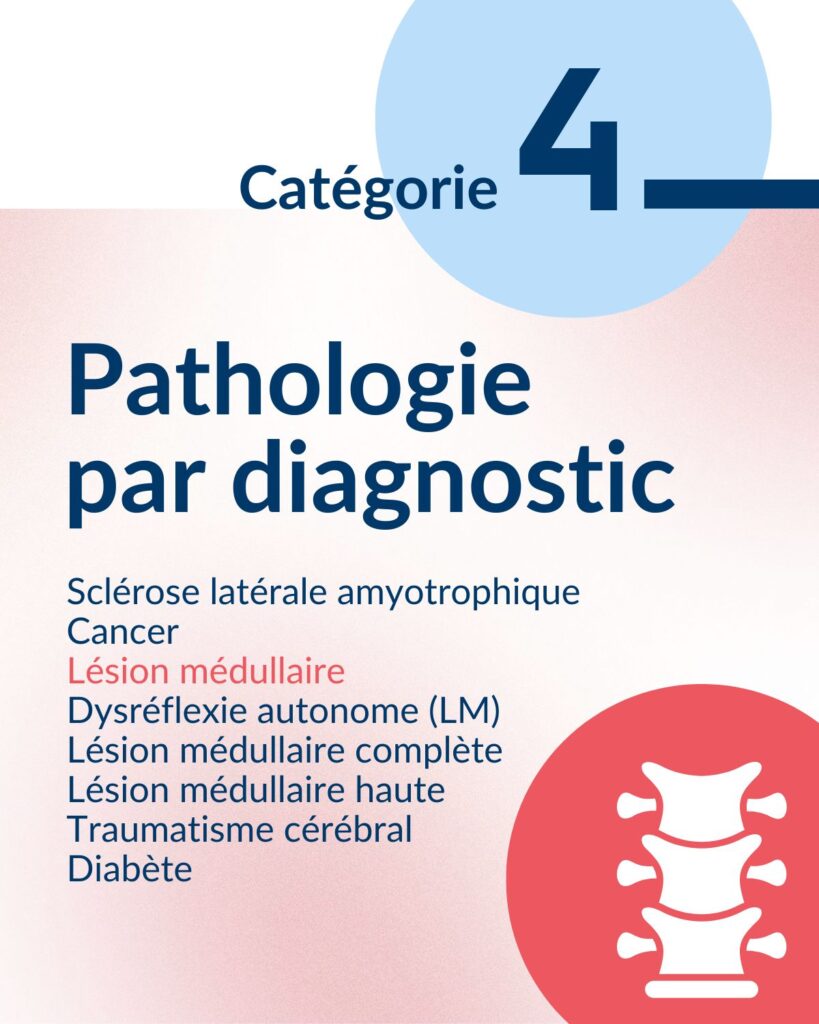

Les multiples facteurs de risque derrière les plaies de pression

Une synthèse de la littérature existante a permis d’identifier les multiples facteurs personnels associés à l’apparition des plaies de pression et de mesurer leur importance.